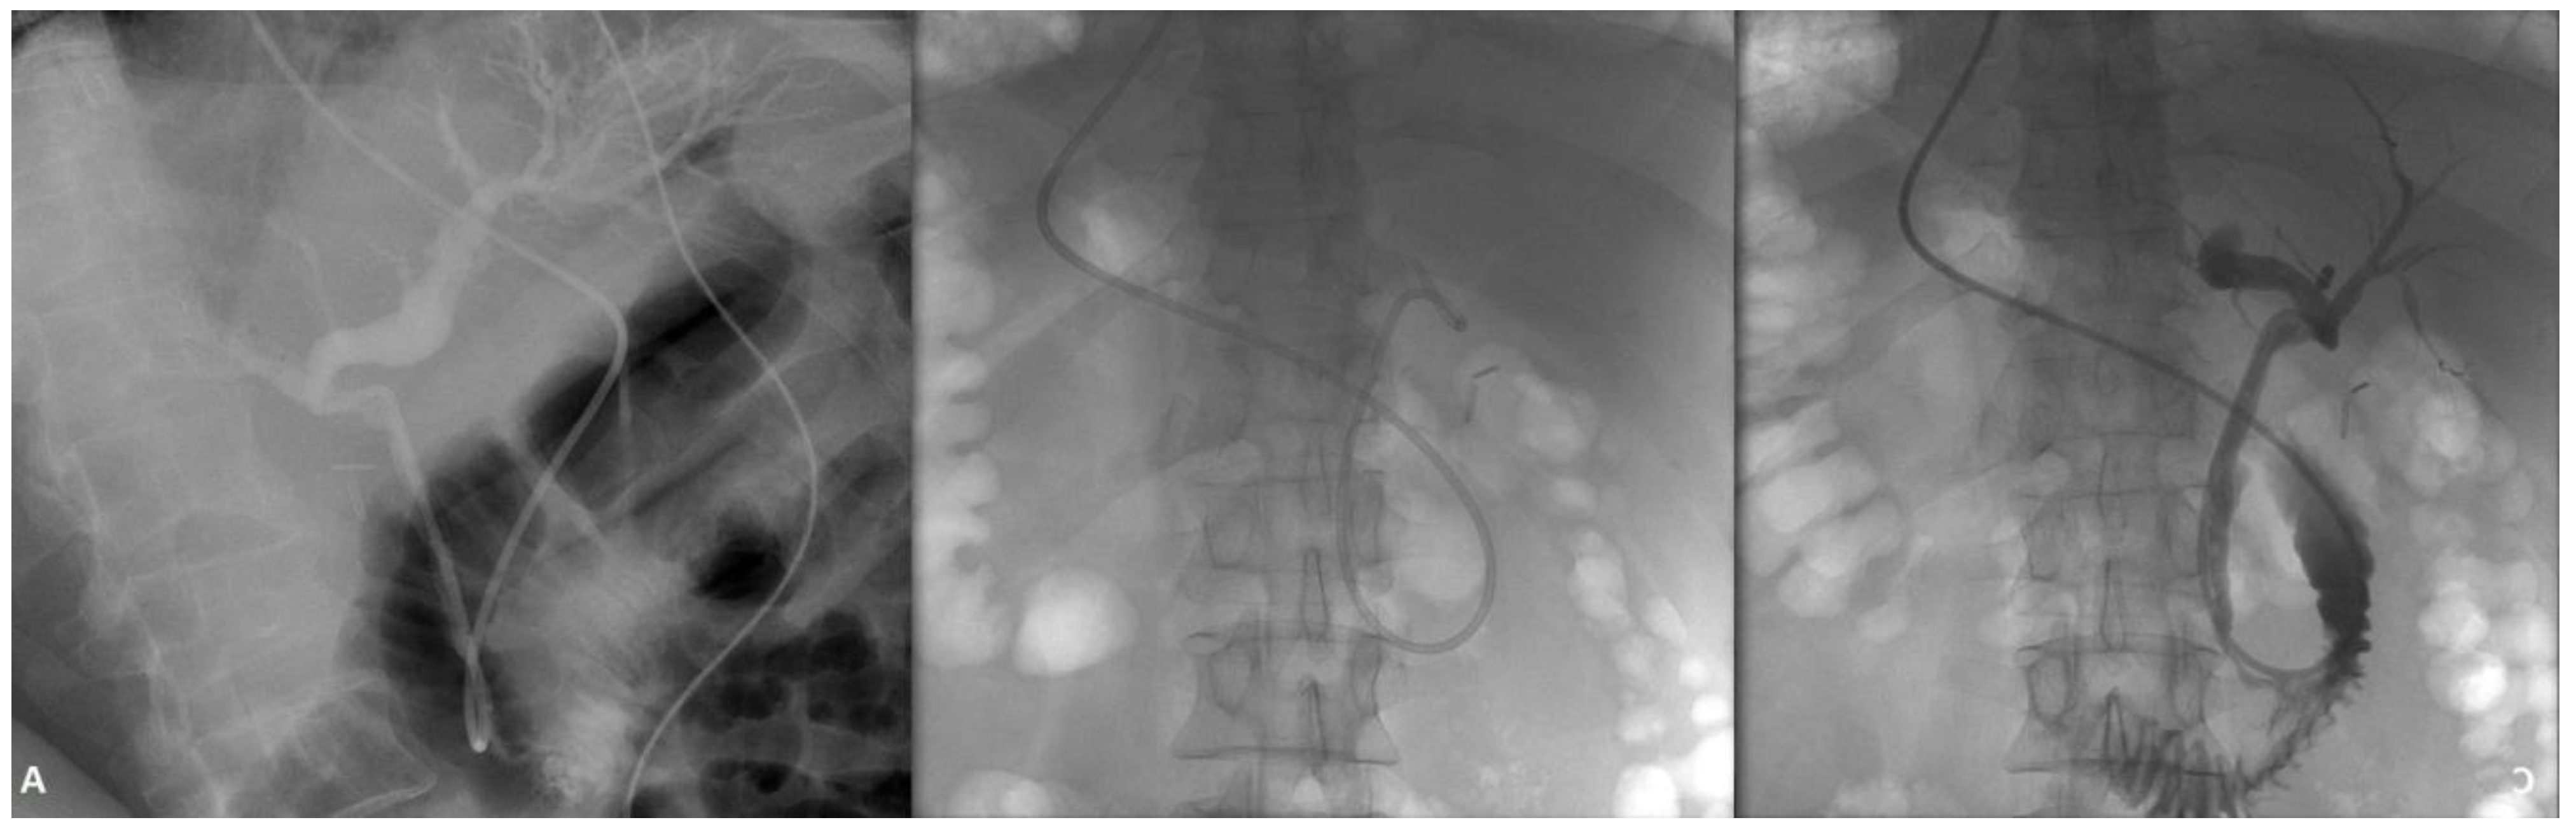

ERCP was performed with difficulty due to the patient's anatomical particularities, but initially the patient was placed in supine position, with the endoscopist turned with his right side toward the patient and then prone position was adopted when advancing the scope into the duodenum. A stable position in front of a macroscopically normal papilla was gained and facile biliary access quickly followed, with contrast injection showing a common bile duct (CBD) of 6 mm with filiform morphology of the distal CBD and no lacunary image along the duct. Extraction ballon was then used to control the CBD, but during this procedure, an intrahepatic biliary lake with lacunary image resembling stone conglomerate emerged the right lobe due to the pressure put up by the balloon inflation.

Figure 1. Normal common bile duct (A), with biliary lake emerging in the right intrahepatic ducts (B and C).